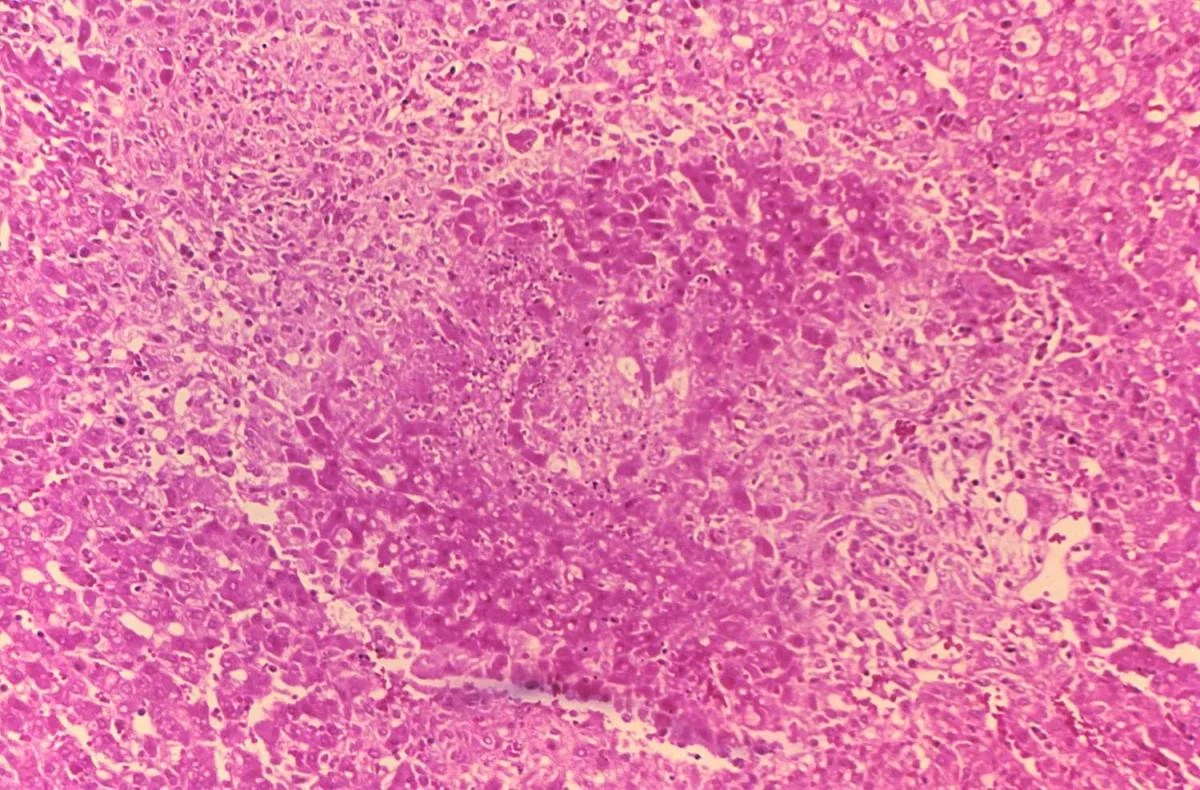

Brucella granuloma Brucella granuloma májban Brucellózis – Brucella suis okozta nekrotikus granuloma sertés májszövetben. Mikroszkópos kép. Forrás CDC, Wikimedia Commons Kategória Diagnosztika Közzétéve: 2020. 11. 12. 12:58 You must have JavaScript enabled to use this form. Saját név Hozzászólás A szövegformátumokról Egyszerű szöveg A HTML jelölők használata nem megengedett. A webcímek és e-mail címek automatikusan kattintható hivatkozásokká alakulnak. A sorokat és bekezdéseket a rendszer automatikusan felismeri. A mező üresen hagyandó